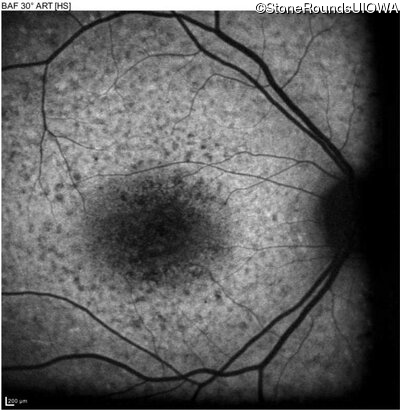

AR Stargardt Disease (IIA)

Age at visit: 15 years

This 15 year old female recalls not being able to see the black board in 2nd grade despite sitting in the 2nd row.

AR Stargardt Disease ABCA4 Val256Val GTG>GTT His1118Asp CAC>GAC AR